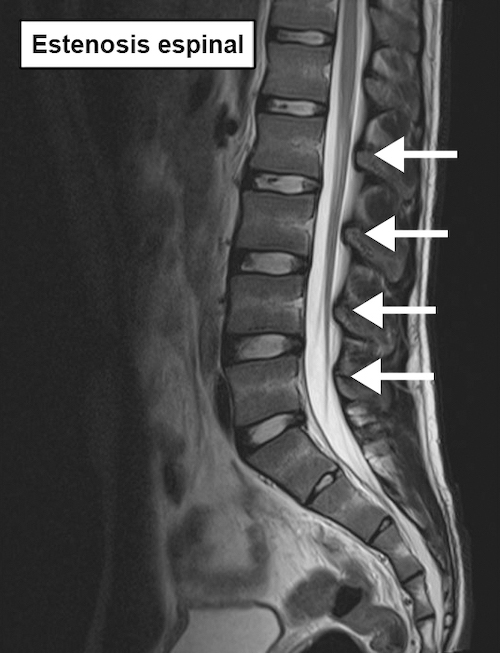

La columna vertebral se estrecha en caso de estenosis espinal. Esto provoca el pinzamiento de una o varias raíces nerviosas. Los nervios afectados pueden causar dolor en las piernas al caminar. También se denomina claudicación neurogénica.

La columna lumbar está formada por las vértebras de la parte inferior de la espalda. Las vértebras se apilan unas sobre otras y forman un largo canal vertical. Un gran haz de nervios atraviesa este canal. En el caso de la estenosis del canal de la columna espinal lumbar, el canal se estrecha y esto puede provocar el pinzamiento de las raíces nerviosas en el canal. El resultado son síntomas en la zona inervada por la raíz nerviosa.

El diagnóstico se realiza en base a la exploración física y los síntomas. Las radiografías, el TAC y la resonancia magnética pueden ser útiles para visualizar el estrechamiento y determinar su localización exacta.